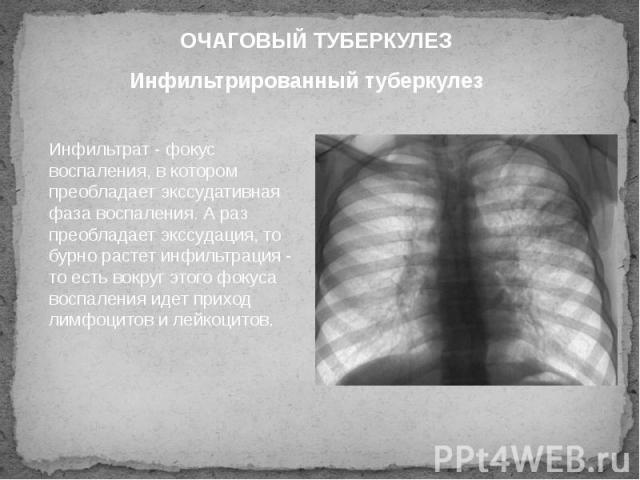

Иллюстрации по теме очагового и инфильтративного туберкулеза